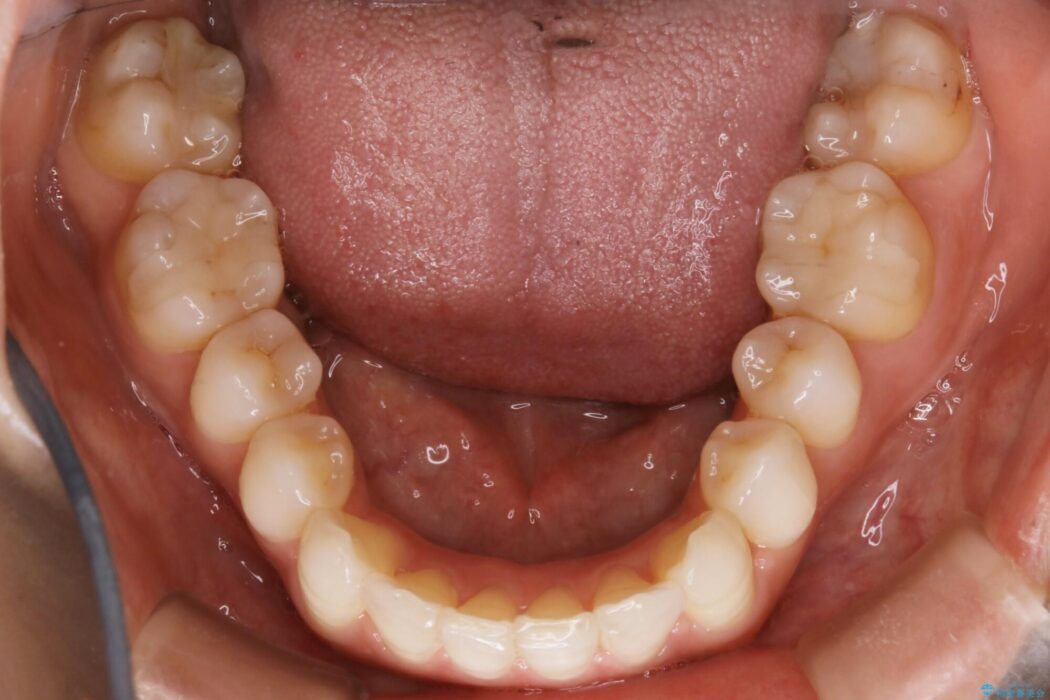

既定のインビザラインの装着時間を守っていただけたこともあり整ったアーチとなりました。

特に気にされていた噛み合わせは改善されご満足いただけました。